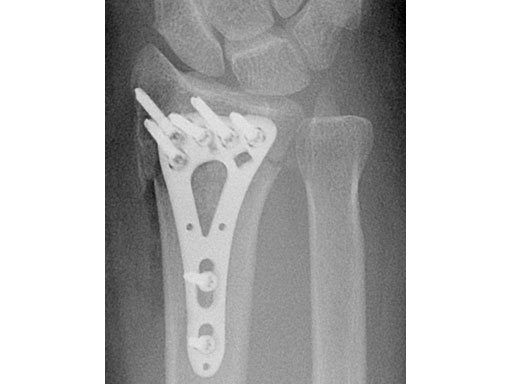

A young woman, 1,5 m tall, 45 kg, sustained a very distal C1.1 fracture of the distal radius.

Fig 3ac Postoperative x-rays showing comparison of plate alternatives.